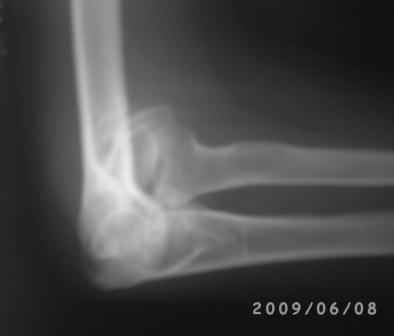

Уважаемые коллеги! Обратился больной 17 лет с жалобами на деформацию пр. локтевого сустава.

Травму получил 7 лет назад. Локально: вальгусная деформация л/с под углом 45гр., сгибание -30, разгибание-170гр., наружный мышелок плеча под пальцами подвижен, что интересно- мышелок плеча при пронации и супинации п/плечья вместе с головкой луча поднимается и опускается( см снимки).

Уважаемый Женя! Имеется ложный сустав 7-летной давности, за этом время рос только медиальный мышелок, а лат. мышелка почти не

осталось. имеется только головчатое возвышение, полностью заполнять дефект чипсами или аутопластикой технически невозможно, и это привело бы к импинджменту плече-лучевого сустава, а остеосинтез оставшейся части мышелка к плечевой кости может решать только вопрос ложного сустава, а вальгусная деформация так и остается, поэтому я планировал сначала восстановить биомеханику логичным и проверенным путем- надмышелковой остеотомией плечевой кости. А дальше надо хорошо ортопедически все продумать, и здесь необходим опыт и знания наших ученых и старших уважаемых ортопедов Форума, я очень надеюсь на это!